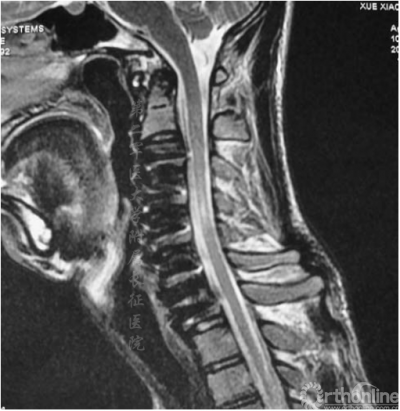

图1.术前侧位MRI显示脊柱后凸,支点在C4-C5水平,颈脊髓明显萎缩

颈椎中立位MRI可见颈椎后凸在C4-C5或C5-C6处具有顶点(图1),且脊髓出现轻度萎缩。屈颈位MRI可见硬膜外高信号影及硬膜囊后壁前移(图2)。头颅MRI未显示异常。根据MRI将患者诊断为平山病伴颈椎后凸畸形。入院三天后,患者在全麻下接受颈前路椎间盘切除术并在C3-C7水平融合以重建颈椎序列和脊柱前凸(图3)。